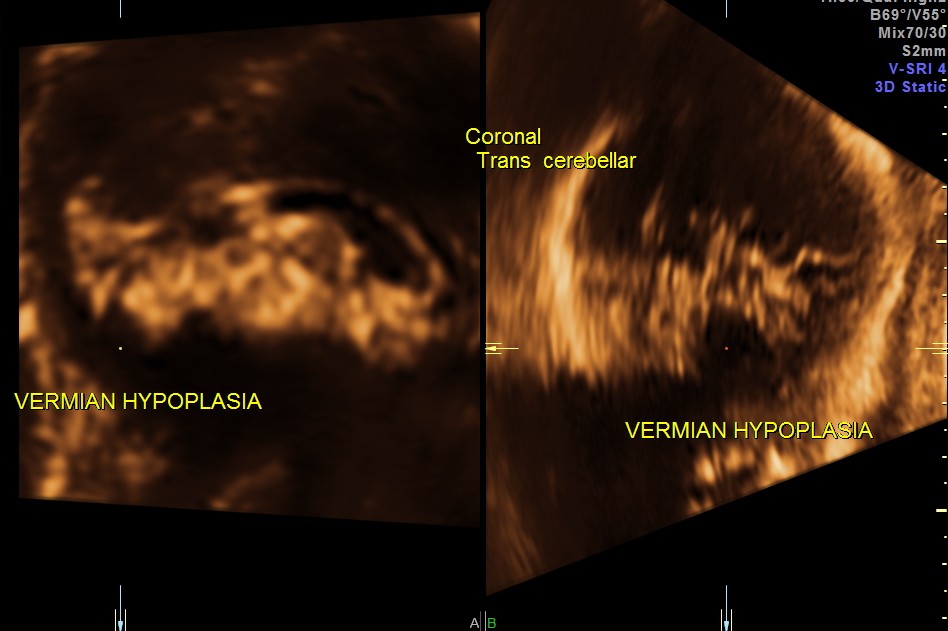

Ultrasound pictures of the fetal cranium are given below and showed cerebellar vermian dysgenesis .The buttocks sign can be appreciated.